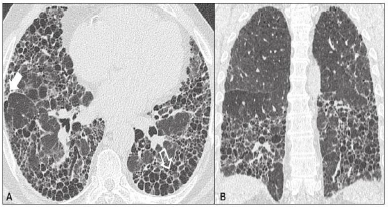

Paciente 56 anos, tabagista (35 anos/maços), refere dispneia e

tosse seca, há 9 meses, de caráter progressivo, associado à

perda ponderal de 3 kg. Relata ser hipertenso, em uso de

captopril 25 mg, 3x ao dia, e fazer tratamento para doença do

refluxo gastroesofágico, há 2 anos. Tem histórico de trabalhar

na lavoura, por 15 anos, e exposição prévia a mofo, em sua

residência. Ao exame físico, apresenta baqueteamento digital

e, na ausculta, tem crepitações em terço médio bilateral.

Disponível em: www.rb.org.br

Diante do quadro clinico e associado às imagens da tomografia de tórax, qual o diagnóstico mais provável?